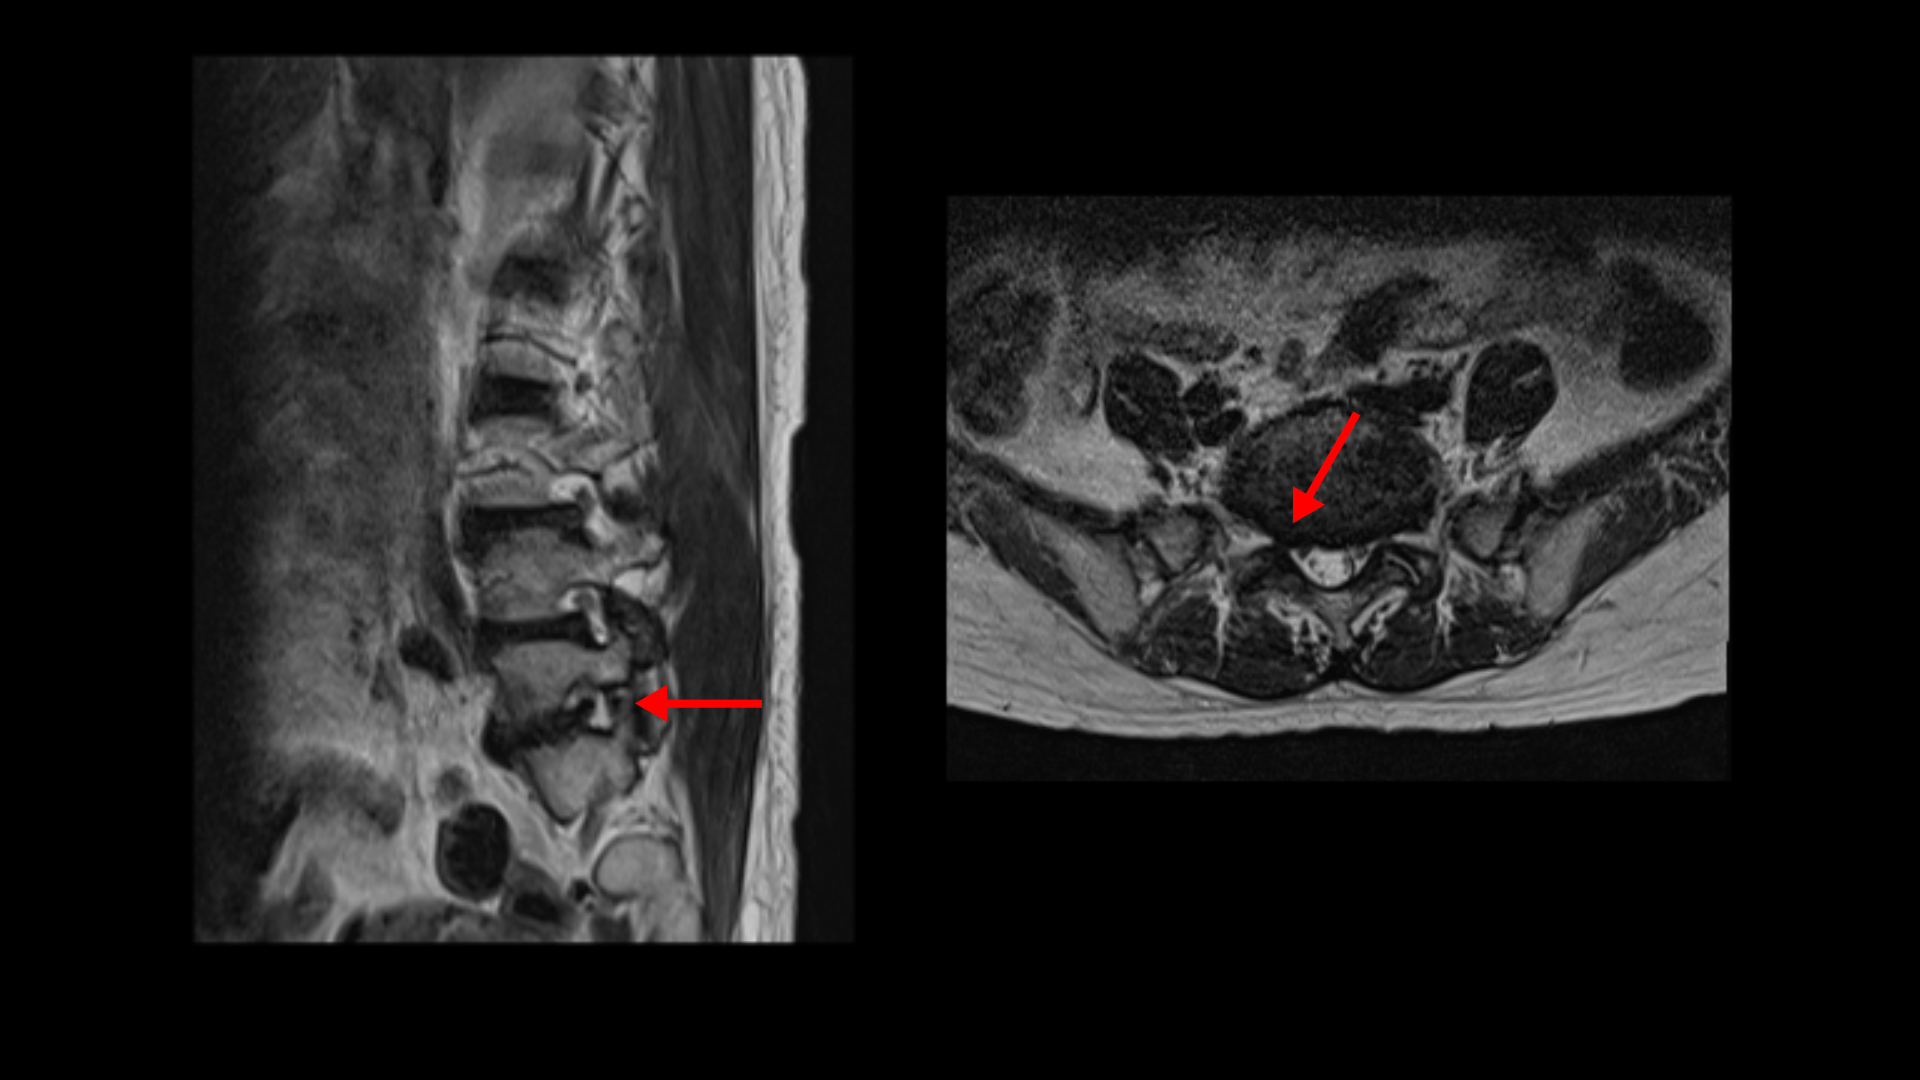

이 전방전위증 때문에 척추관에 중심성 협착도 있습니다.

4번 5번 디스크가 중앙에서 우측으로 약간 밀려 나와있고

>또 5번 1번에서는 신경이 빠져나가는 오른쪽 추간공이 약간 좁아져 있습니다.

그런데 이분 허리 MRI를 자세히 보면 딱히 신경이 아주 극심하게 눌린 곳도 없습니다.

신경이 조금 눌릴 수는 있어도 심각해 보이지는 않습니다.

신경구멍이 지나가는 길이 여러 가지 퇴행성 변화로 조금씩은 좁아져 있지만 굳이 수술로 특히 여러 마디의 나사를 박는 수술까지 해가며 신경압박을 해소해야 할 정도의 심한 신경눌림은 보이지 않는 겁니다.